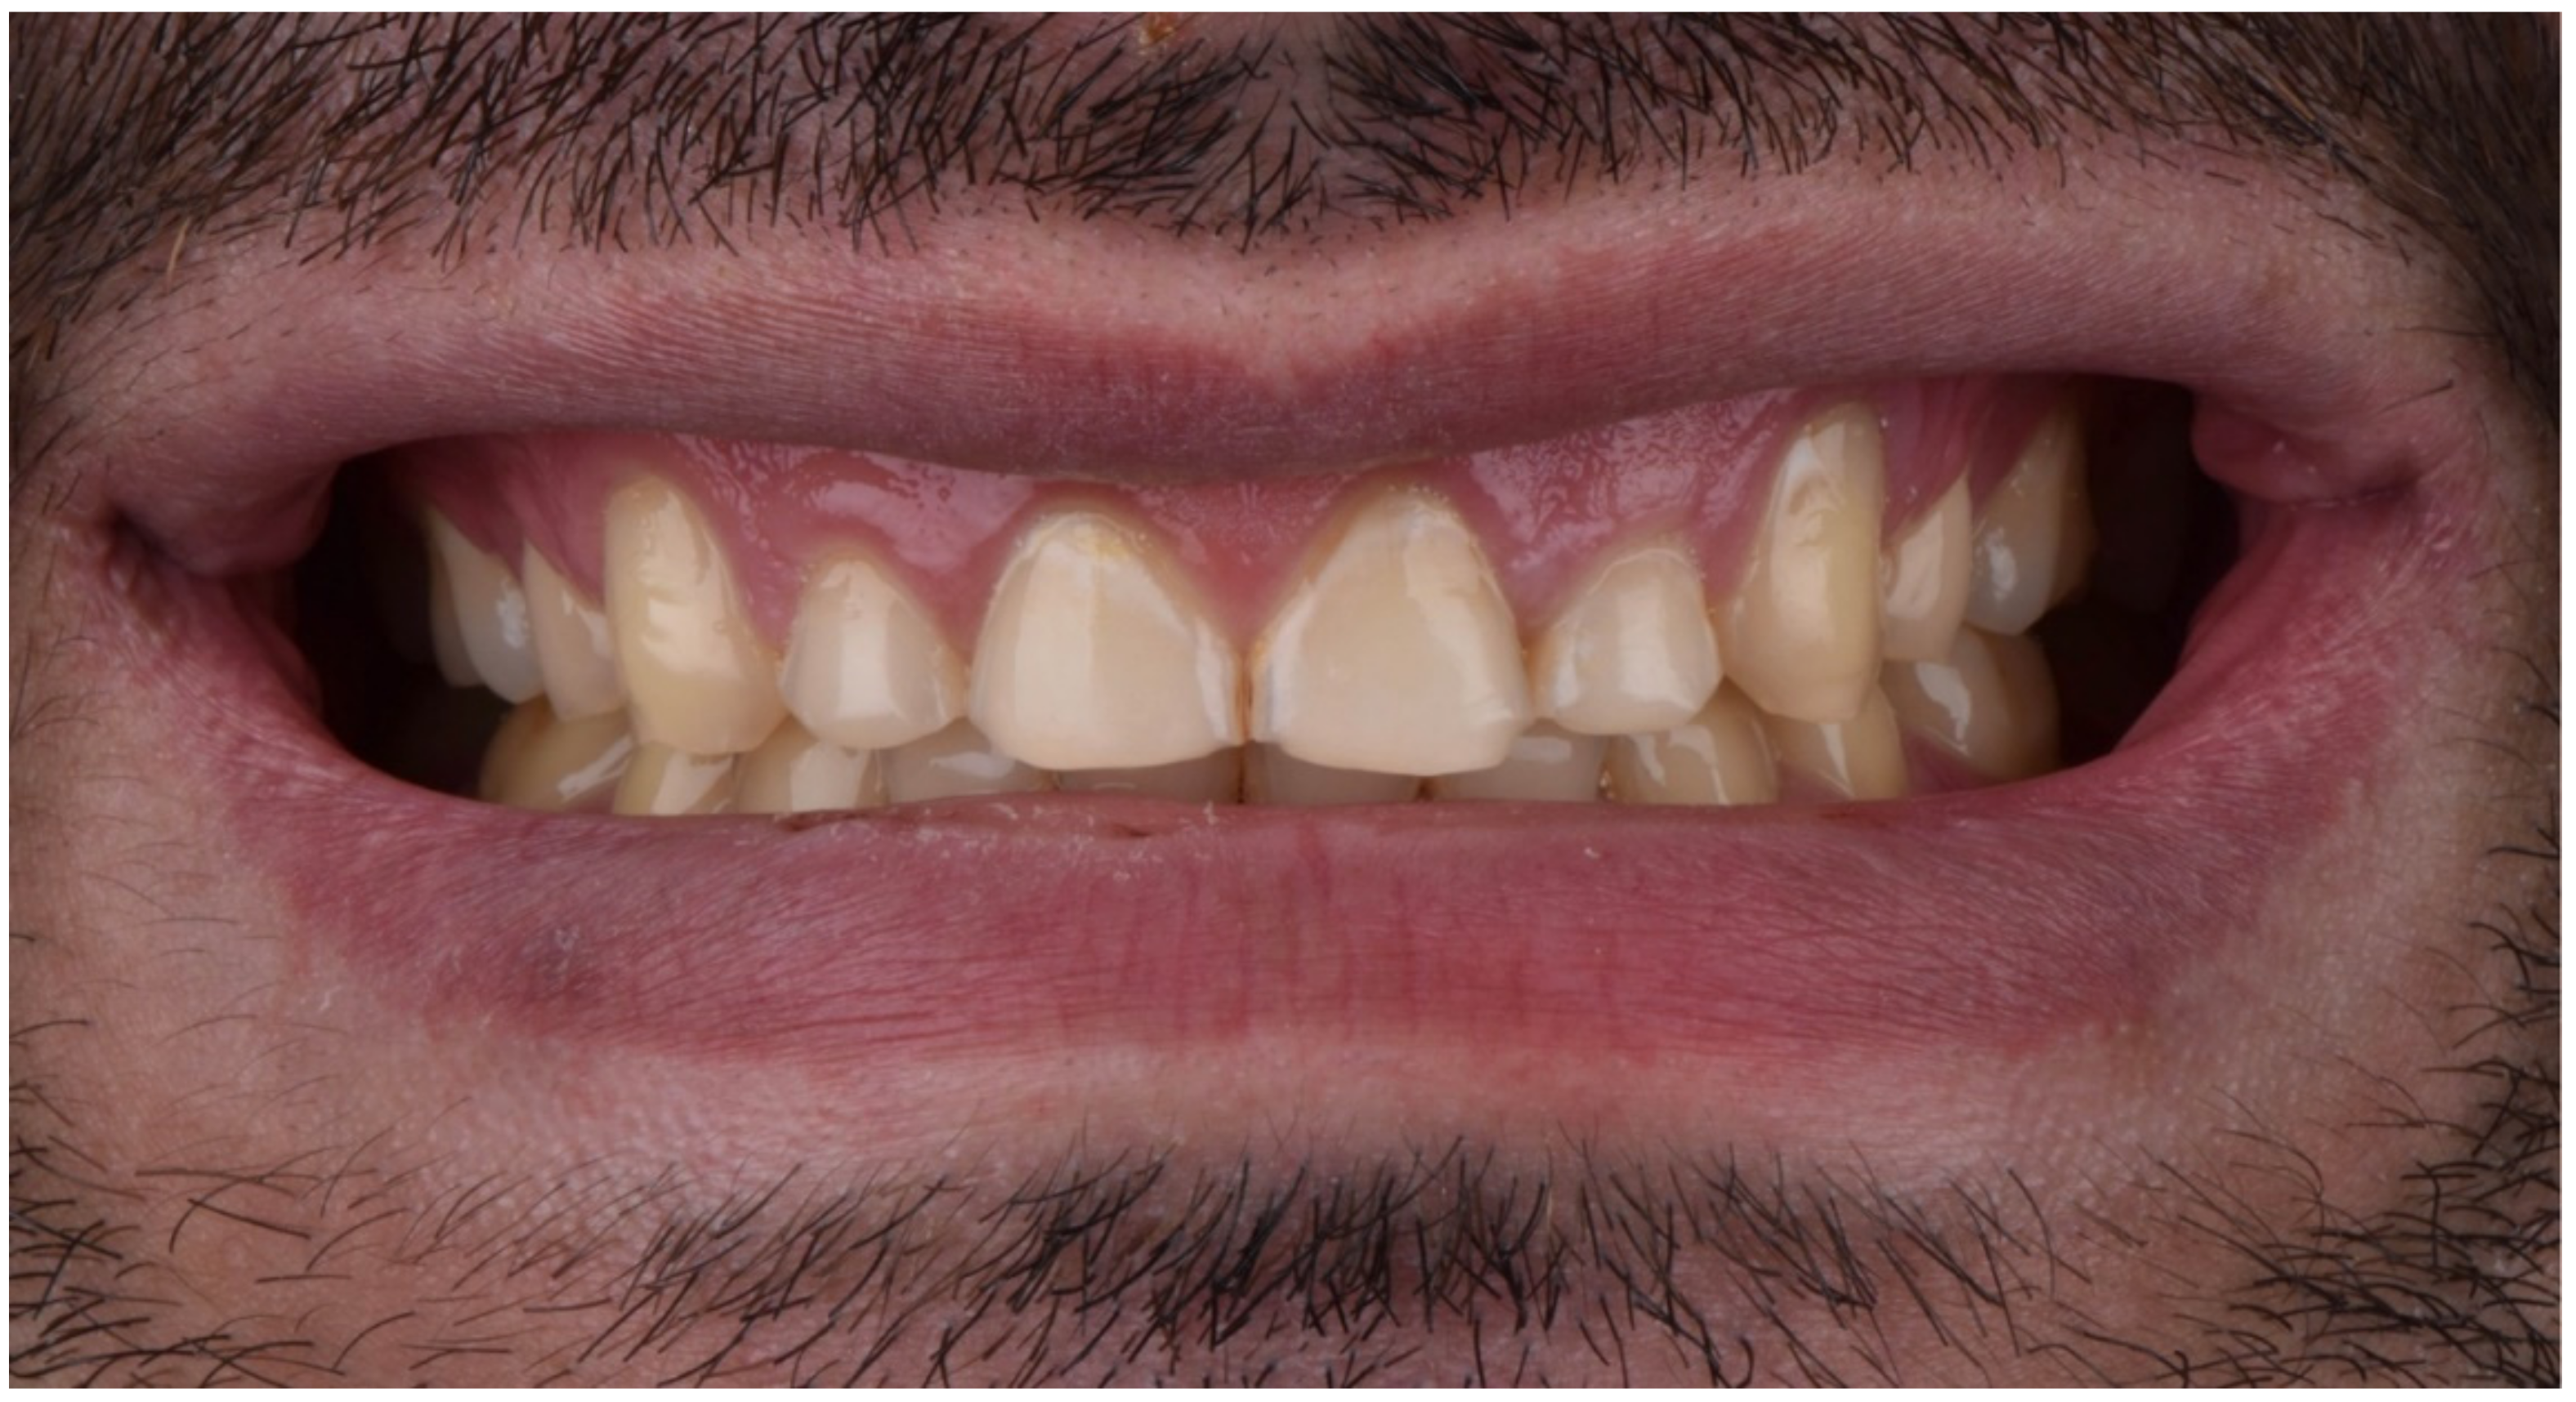

2. Clinical Report

2.1. Planning Phase

2.2. Restorative Phase